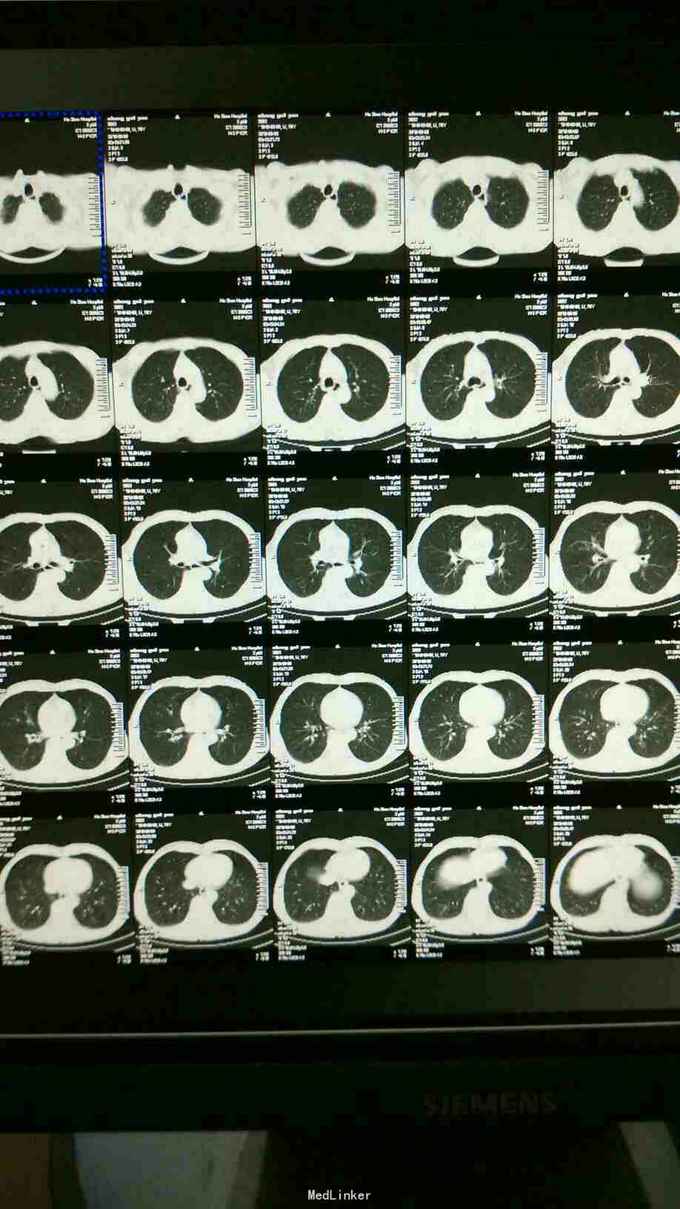

患者男70岁,主因两侧肋部疼痛三天来诊 ,患者三天前不明原因两肋部疼痛,与呼吸关系不大,既往高血压病史,一直服药控制,来院查体体温正常,听诊未见异常,心电图正常。拍肺部ct正常

肋间神经?

大家考虑什么原因?